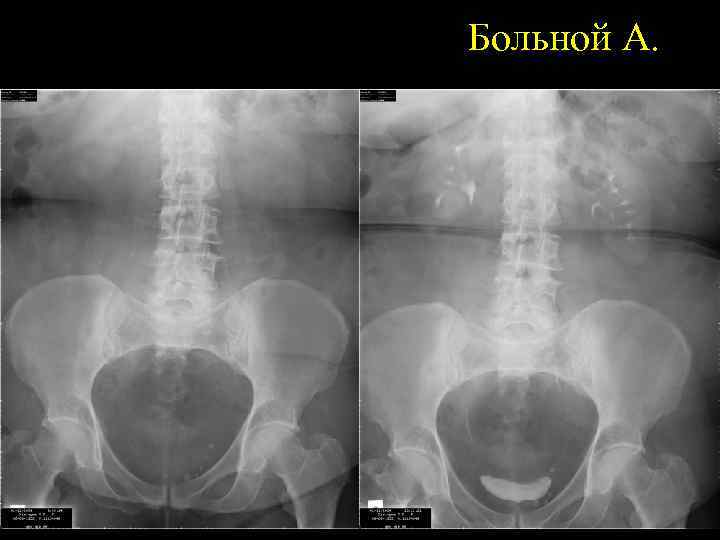

Больной А.